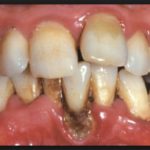

Стоматологи выделяют три степени протекания болезни. На первой и самой легкой стадии образуется карман в десне глубиной до 4 мм. Пока ощущения неприятные, но терпимые. Изменения в костной ткани еще не начались. Средняя степень тяжести характеризуется увеличением глубины кармана до 6 мм. Такой периодонтит симптомы имеет более явные: корни зубов слегка оголяются, десны воспалены, зубы становятся подвижными. Тяжелая стадия – это карман глубиной уже до 9 мм, сильное нагноение. Зубы меняют свое положение, а их подвижность настолько сильная, что не позволяет нормально питаться.

Гранулирующий периодонтит вызывает сильную боль в пораженном зубе, отек десны, при котором она может приобрести даже синий оттенок. Болевые ощущения возникают в форме приступов и усиливаются при жевании или температурном воздействии (когда человек ест мороженое, пьет горячий чай). Обострение периодонтита провоцирует формирование свища с серозным или гнойным содержимым. Его ход открывается на шее или лице, и после разрыва образования с последующим оттоком гноя возникает временное облегчение, после чего болезнь переходит в хроническую фазу.